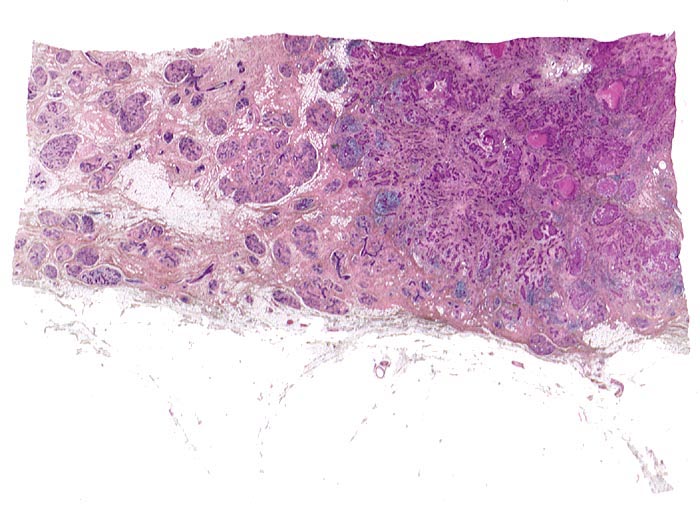

invasives duktales Mammakarzinom

Links im Bild normale Drüsenläppchen. Rechts das Karzinom ohne erkennbare Läppchenstruktur mit Entzündungsinfiltraten im Bereich der Invasionsfront und herdförmigen Tumornekrosen.

Makroskopisch: derber weisser Herd von 2.2cm Durchmesser im oberen äusseren Quadranten.

Die Patientin hatte bei der Selbstuntersuchung einen harten Knoten in der rechten Mamma palpiert. Nach dem Nachweis von Karzinomzellen in der Feinnadelpunktion wurde eine Lumpektomie durchgeführt. Die intraoperative Schnellschnittuntersuchung ergab tumorfreie Resektionsränder.